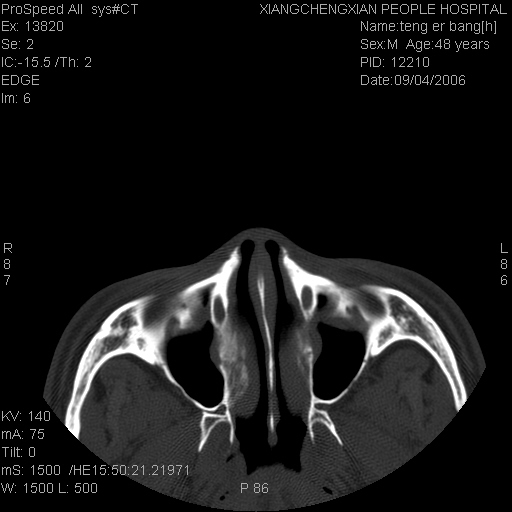

患者,男,以头面部外伤后头疼1小时为主诉入院,患者1小时前被他人打伤头部及左侧面部,眼睑无水肿,左侧面部肿胀压疼,未触及骨擦音。专科检查:耳鼻喉未见异常。

ct:平扫+冠扫:双侧鼻骨对比,冠扫s6#示右侧鼻骨尖部可见线状低密度影,边缘光滑,并见硬化.软组织未见肿胀.

诊断意见:鼻额缝(鼻骨与上颌骨额突缝),但个别同志认为是骨折.因此请同行们会诊.多谢了!

正常鼻颌缝。软组织无肿胀。鼻腔无积液积血。鼻骨光滑规整无中断。均不支持骨折。

正常的,双侧对称.边缘光整,且逢等宽.

正常鼻颌缝。软组织无肿胀。鼻腔无积液积血。鼻骨光滑规整双侧对称。均不支持骨折。